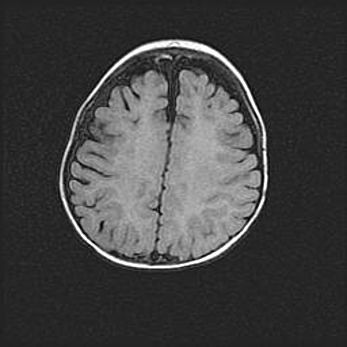

Сообщающаяся гидроцефалия. Кистозная энцефаломаляция головного мозга.

Возраст: 3 месяца 4 дня

Вес: 3100 г

Пол: женский

Окружность головы: 34 см

Срок гестации: 31 неделя

Кистозная энцефаломаляция головного мозга - одна из форм поражения головного мозга в детском возрасте. Характеризуется возникновением множественных и распространённых кист в коре, белом веществе и подкорковых образованиях головного мозга у плодов, новорождённых и детей раннего возраста. Развитие кистозной энцефаломаляции связано с внутриутробной асфиксией и гипотонией, родовой травмой, тромбозом синусов, пороками развития сосудов, инфекциями, сепсисом и другими причинами. Наиболее значимые инфекционные агенты: вирусы простого герпеса, цитомегалии, краснухи, токсоплазмы, энтеробактерии, золотистый стафилококк и другие.